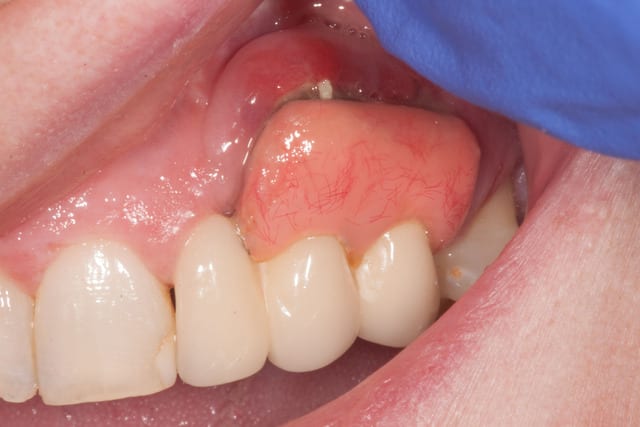

Cliniquement, si la 22 a été réalisée de façon classique, 23 et 24 sont montée sur une armature métallique en selle. En palatin, la selle avance sur le palais de 2 mm, mais en vestibulaire, on est plus à 8 mm de recouvrement.

La formation de tartre dans l'intrados de la selle donne une gencive inflammatoire, saignant spontanément au passage d'un fouloir rond. Je vous laisse voir les photos.